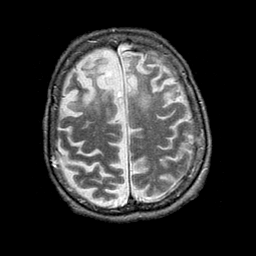

Pick's Disease, MR Study mr-t2 -- Slice #17

[Home][Help][Clinical] Slice 17